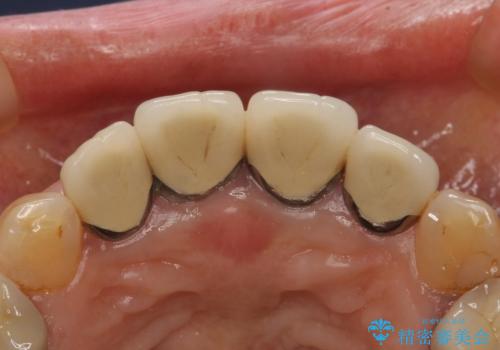

- 前歯のセラミック治療から5年経過した患者様です。

数年ぶりにメンテナンスに来て下さいました。

治療した上の前歯4本は全く問題がないそうで、「どうしてこんなに長持ちするんですか?」と聞かれた程です。

5年前のクラウン装着時と比較したところ、歯肉が成熟し歯間乳頭ができており、より天然歯のように自然に見えました。

患者様の良好なセルフケアと精密な適合の良いクラウンにより、歯肉の腫脹や退縮も認められませんでした。

クラウンの種類:ジルコニアオールセラミッククラウン スタンダード